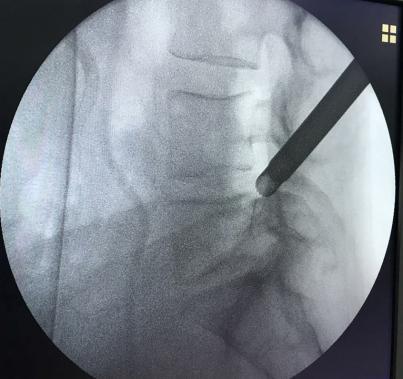

• 不同入路脊柱内镜手术治疗L4/5节段脱垂型腰椎间盘突出症的疗效比较

摘要:目的 观察经椎间孔入路内镜下腰椎间盘切除术(TELD)和经椎板间入路内镜下腰椎间盘摘除术(IELD)治疗L4/5节段脱垂型腰椎间盘突出症(LDH)的临床疗效。方法 回顾性分析2020年11月-2022年11月该院采用脊柱内镜手术治疗的75例L4/5节段脱垂型LDH患者的临床资料。根据手术入路的不同,将患者分为TELD组(53例)和IELD组(22例)。比较两组患者的手术情况和术后疗效。结果 与TELD组比较,IELD组的手术时间明显缩短,术中透视次数明显减少,差异均有统计学意义(P < 0.05);两组患者住院时间和并发症发生率比较,差异均无统计学意义(P > 0.05)。所有患者术后均获得12~19个月的随访。两组患者末次随访时的视觉模拟评分法(VAS)评分和Oswestry功能障碍指数(ODI)明显低于术前,且IELD组明显低于TELD组,差异均有统计学意义(P < 0.05)。按照突出物和神经根的不同位置进一步分析,两组肩上型患者(TELD组10例,IELD组6例)末次随访时的VAS评分和ODI明显低于术前,且IELD组末次随访时的VAS评分明显低于TELD组,差异均有统计学意义(P < 0.05);两组腋下型患者(TELD组8例,IELD组16例)末次随访时的VAS评分和ODI明显低于术前,且IELD组明显低于TELD组,差异均有统计学意义(P < 0.05);35例肩前型患者经TELD术后,末次随访时的VAS评分和ODI明显低于术前,差异有统计学意义(P < 0.05)。按照突出物的不同Lee分区进一步分析,两组Lee Ⅲ区患者(TELD组44例,IELD组10例)末次随访时的VAS评分和ODI明显低于术前,且IELD组的ODI明显低于TELD组,差异均有统计学意义(P < 0.05);两组Lee Ⅳ区患者(TELD组9例,IELD组12例)末次随访时的VAS评分和ODI明显低于术前,且IELD组明显低于TELD组,差异均有统计学意义(P < 0.05)。结论 采用TELD和IELD治疗L4/5节段脱垂型LDH,均可获得较满意的减压效果,但IELD的手术时间相对较短,X线透视次数较少,且对肩上型、腋下型、Lee Ⅲ区和Lee Ⅳ区的减压效果更有优势。